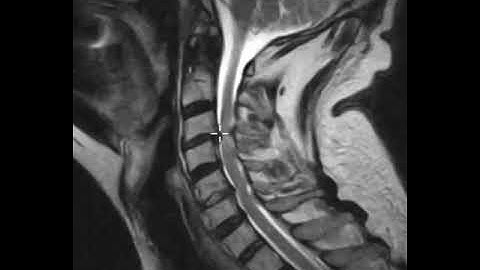

Mri of cord compression